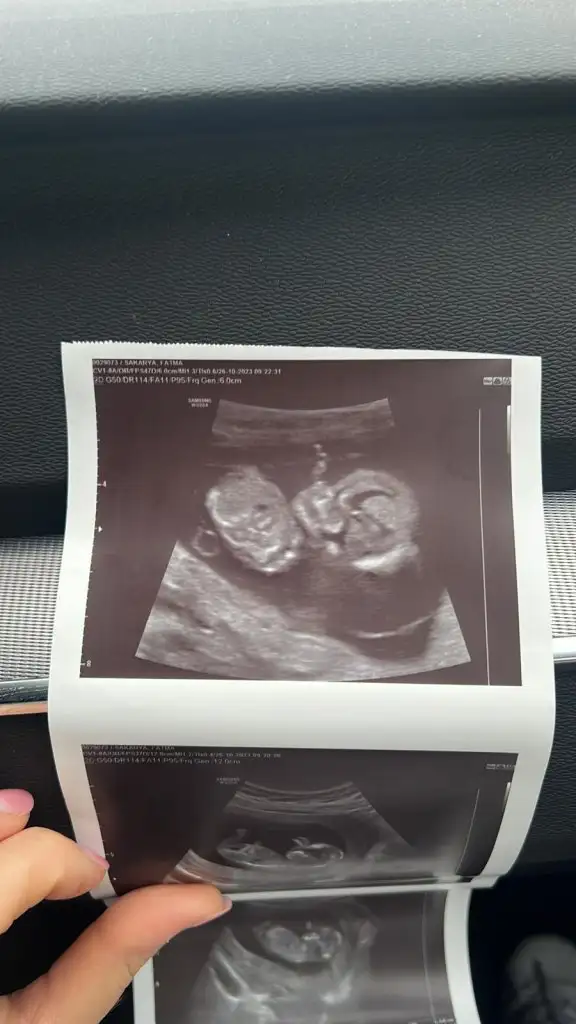

12+1 tahmin yapabilir misjniz

12 haftalik

12 haftalik bakarmisiniz cinsiyete?